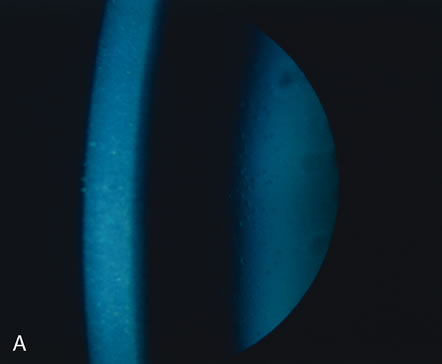

AXENFELD'S ANOMALY

Isolated Axenfeld's anomaly (posterior embryotoxon) consists of a clinically prominent Schwalbe's line (terminal end of Descemet's membrane) plus a variable number of iris processes extending from the peripheral iris to Schwalbe's line (Fig. 6). The condition is most likely a developmental arrest, late in gestation, of tissues derived from neural crest cells.66 The line appears as a deep linear opacity of the peripheral cornea of variable prominence and extent and is most often found temporally. The prevalence rate is approximately 15% to 25%.67,68 No race or sex predilection exists. Although the majority of the eyes are normal, an associated partial iris coloboma and other anomalies may occur.68 Axenfeld's anomaly may be associated with non-ocular abnormalities as part of Axenfeld-Rieger's syndrome (see later).

Fig. 6. Axenfeld's anomaly (posterior embryotoxin). A. The only abnormality visible from the 2-o'clock to 4-o'clock positions adjacent to the limbus is a “ropy” corneal opacity. The other eye is normal. B. A corneal opacity is present over 360 degrees near the limbus at the level of Descemet's membrane. C. Scanning electron micrograph shows the iris processes spanning the angle and attaching to the anteriorly displaced Schwalbe's ring. Artifactually broken ends of the iris processes are indicated by the arrows. D. Macroscopic appearance of the iris processes attaching to Schwalbe's ring. E. Iris processes attach to the anteriorly displaced Schwalbe's ring. (Courtesy of SEI Photoarchives.)

Histologically, Axenfeld's anomaly consists of dense collagen and ground substance covered by a monolayer of flattened endothelial or spindle-shaped cells at the terminal end of Descemet's membrane. The endothelium is contiguous with the endothelium covering the trabecular beams.68 Associated iris processes are composed of normal-appearing iris stroma.